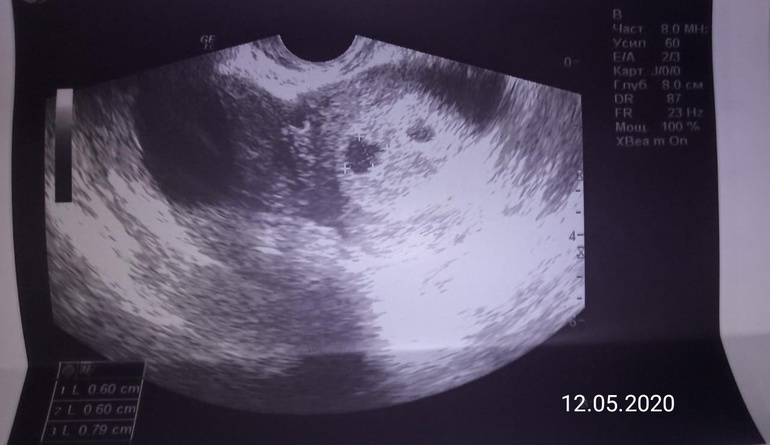

Сходила на узи, 7,5 срок

Пя как положено, ктр эмбриона 15 мм

Сбоку увидели что то и не определили, гематома или второе пя? Вроде пустое.